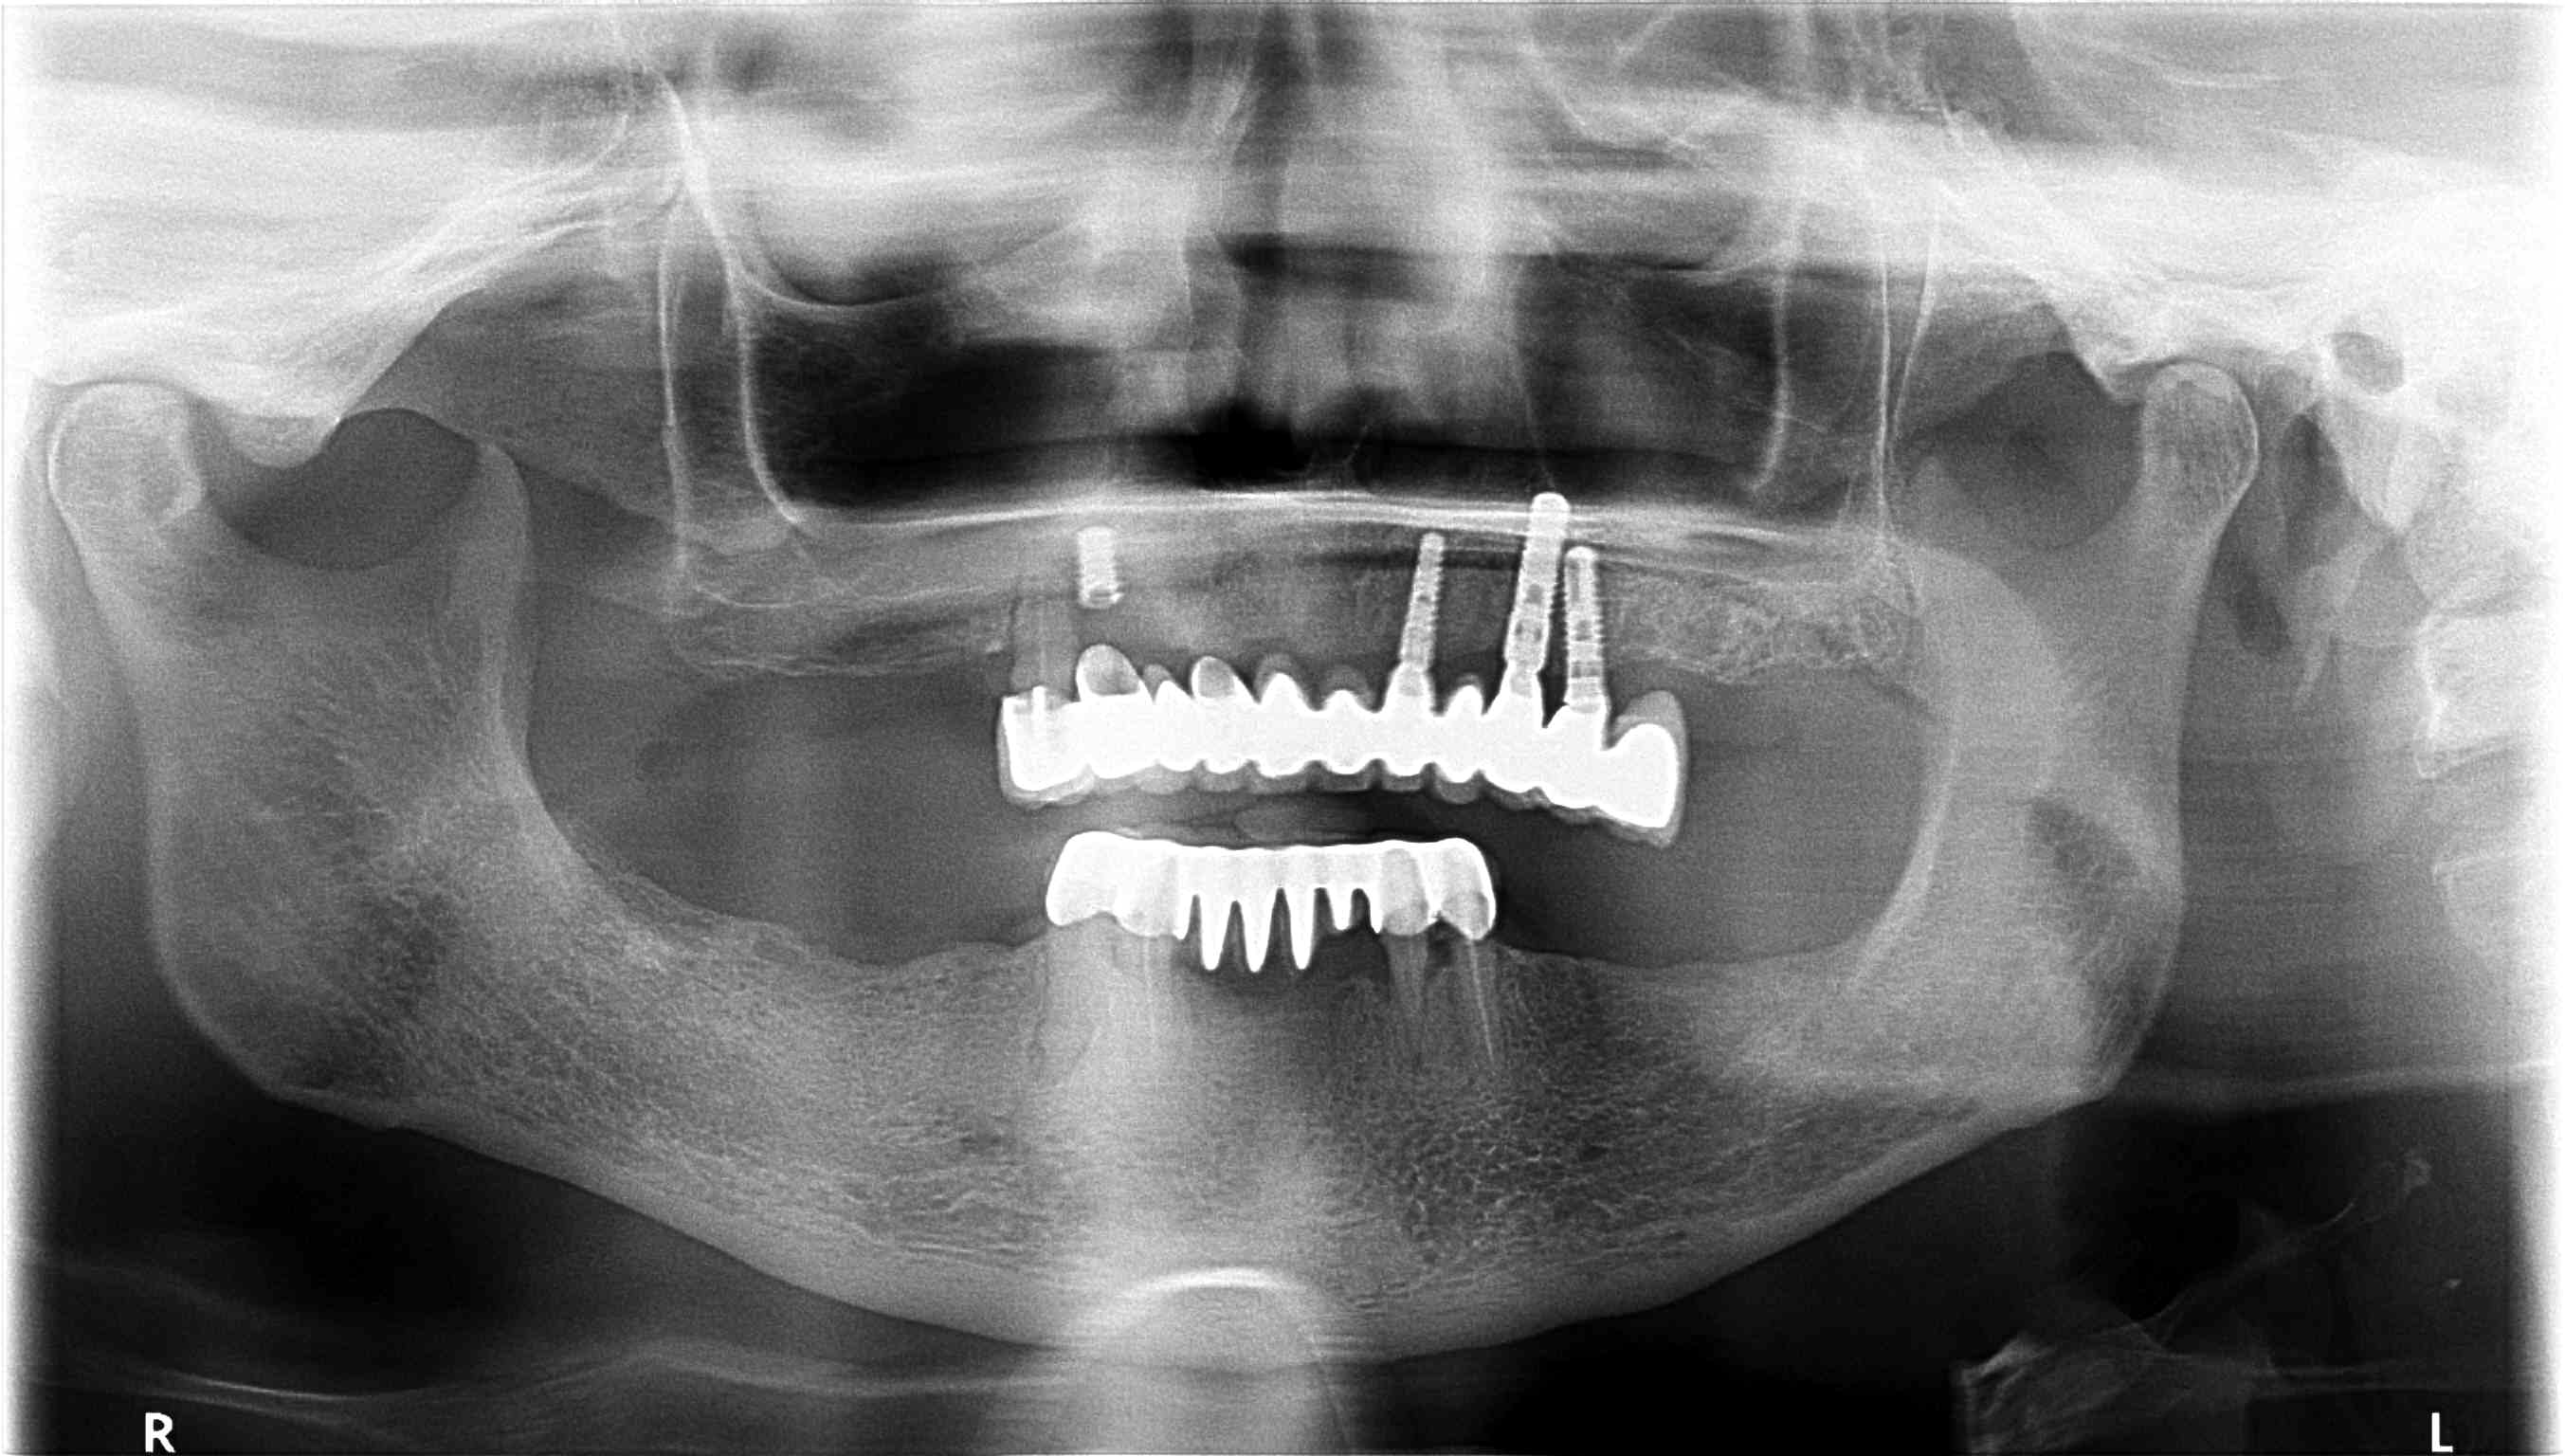

Bonjour pouvez vous m'aider à retrouver la marque de ses implants posés il y 7 ans

Merci